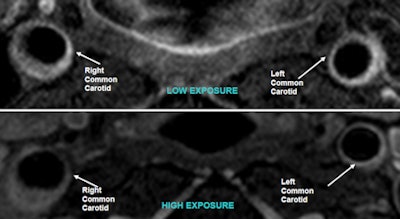

Black-blood MR angiography did not establish a significant difference in carotid plaque burden development between the two sets of workers.

| No significant plaque burden appears in sample carotid images from patients with low (top) and high (bottom) particulate matter exposure. |